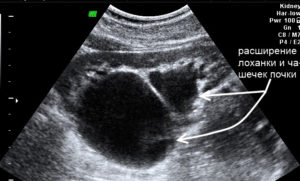

У плода при проведении ультразвукового исследования могут быть обнаружены увеличенные лоханки, чашечки почек, а также увеличенный мочеточник.

Соответственно, врач диагностирует три разных патологии: пиелоэктазию, пиелокаликоэктазию и уретеропиелоктазию.

Структура почки считается одной из самых сложных в организме. Лоханки и чашечки связывают почку с мочевыводящими протоками – мочеточниками. В каждой из крупных лоханок находится несколько больших чашечек. Каждая чашечка, в свою очередь, состоит из чашечек ещё меньших размеров. Специалисты выделяют несколько типов лоханок, которые находятся в почках плода:

Первичное расширение лоханки называется гидронефрозом. Он характеризуется затрудненным оттоком мочи, который вызывается патологическими процессами. Когда лоханка уменьшается в размере – это гипоплазия. В некоторых ситуациях лоханочные составляющие вообще могут отсутствовать.

Пиелоэктазия – это расширение лоханок из-за переполнения их мочой. Они становятся слишком маленькими, для поступающих в них больших объемов мочи и из-за этого растягиваются.

- пиелоэктазия – расширяются только лоханки;

- пиелоуретроэктазия – изменение размера мочеточника и лоханки;

- каликопиелоэктазия – рост всех составляющих чашечно-лоханочной системы.

- пиелоэктазия – изолированное расширение лоханок;

- пиелоуретероэктазия – расширение и лоханок, и мочеточников;

- пиелокаликоэктазия – увеличение размеров и, лоханок, и чашечек;

- гидронефроз – значительное увеличение размеров ЧЛС (10 мм и более), при котором происходит сдавливание паренхиматозной ткани почек, и её функция нарушается.